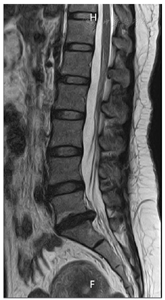

辅助检查:2022年07月20日腰椎MRI示L5/S1椎间盘变性并右后方脱出,S1右侧神经根中心区受压(图1,图2,图3,图4)。

患者慢性病程,反复发作并逐渐加重,以腰腿痛为主诉,无间歇性跛行,无夜间疼痛加重,无潮热盗汗,无二便障碍,完善腰椎MRI提示L5/S1椎间盘变性并右后方脱出、S1右侧神经根中心区受压,诊断LDH并坐骨神经痛。